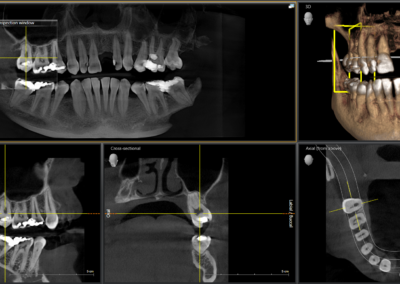

We start with a comprehensive full mouth examination, digital X-rays, a dental 3D(CBCT) scan and Trios5 Scan. The scanned images provide high-resolution images in a three dimensional plane. We use these images and scans for precise treatment planning.

CBCT 3D Scan

Using the 3D images in special planning software, the Dentist maps out the exact position and angle of insertion of each implant. They take care to place implants where they will be stable and in the best position to support the replacement teeth. They will also plan out any bone grafting (if needed) to ensure the implants have strong bone support.